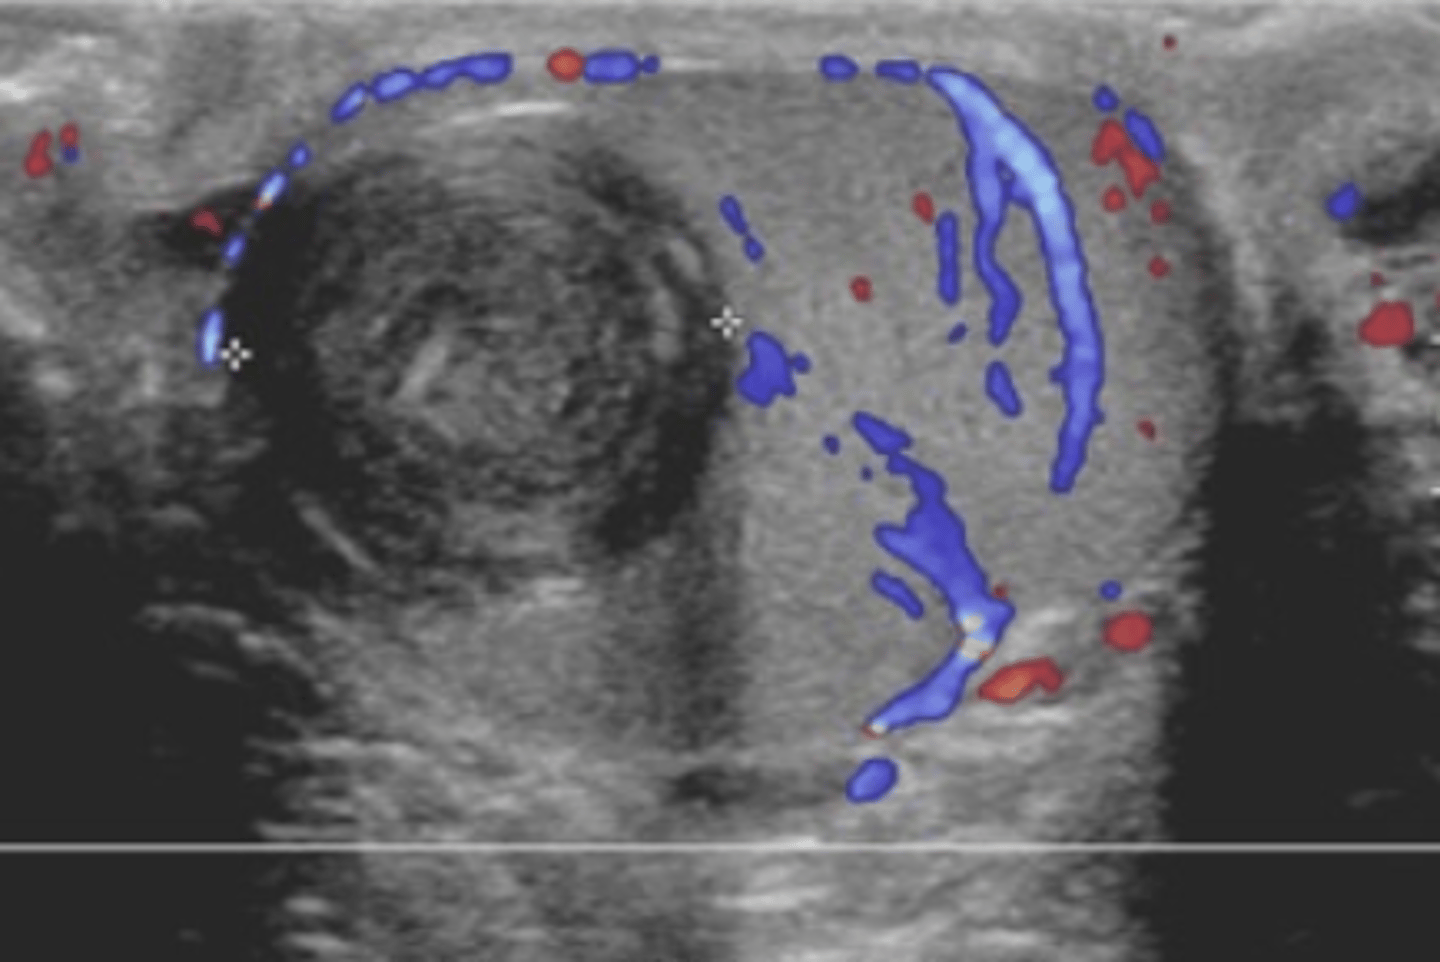

A dilated group of veins found within the scrotum is termed which of the following?

a. Hydrocele

b. Spermatocele

c. Varicocele

d. Hematocele

Which of the following maneuvers is commonly performed during ultrasound to help diagnose a varicocele?

a. Trendelenburg maneuver

b. Murphy maneuver

c. Valsalva maneuver

d. Heimlich maneuver

e. McBurney point

Which of the following venous measurements is most consistent with a varicocele on ultrasound?

a. Dilated veins measuring less than 1 mm

b. Dilated veins measuring greater than 1.5 mm but less than 2mm

c. Dilated veins measuring greater than 2 mm

d. veins should not be dilated